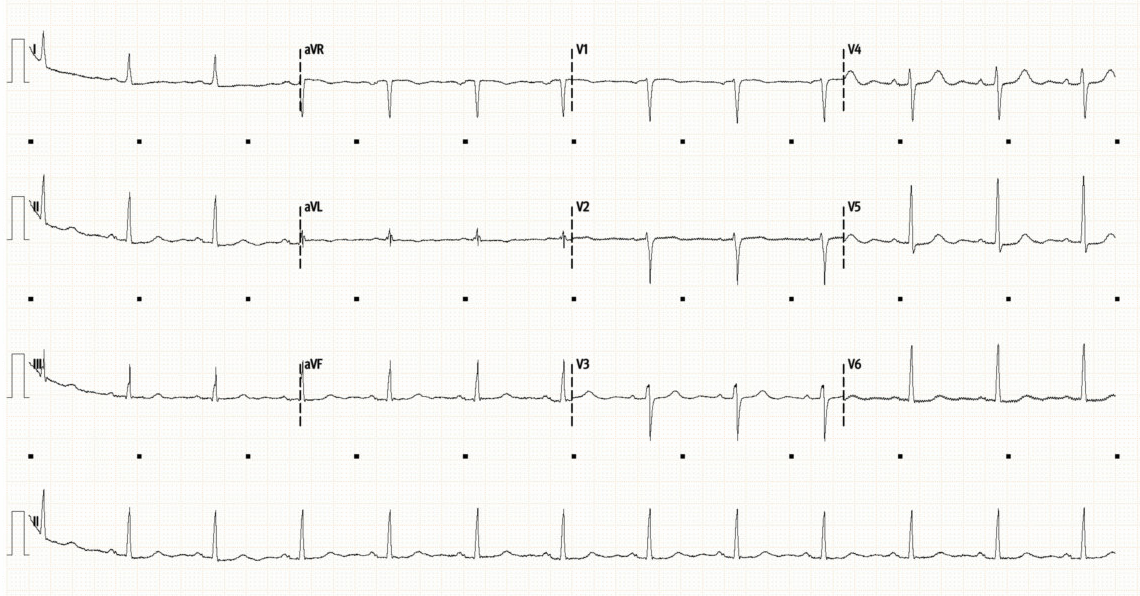

Below is her initial ECG (top), followed by repeat ECG 12 hours later (bottom).

Initial ECG (above), and repeat ECG (below)

• Initial ECG shows a sinus rhythm at 80/min with normal axis and intervals. There are no significant ST or T-wave abnormalities. This is a very unremarkable ECG.

• The repeat ECG shows some dynamic changes compared to prior. There is now subtle ST depression laterally (I, V4-6). There is new T-wave inversion in aVF, as well as new bi-phasic T-waves in V2/3. The T-waves laterally (V5/6) have also flattened compared to the initial ECG.

• Dynamic ECG changes are always concerning for myocardial ischaemia. There is no clear single territory involved here but acute MI needs to be excluded.

The patient had been having intermittent arm pain on initial assessment. At the time of the repeat ECG her pain had resolved. One differential for biphasic T-waves which appear when the patient is pain free is suggest Wellen’s syndrome, and are the result of coronary reperfusion, though typically seen in a vascular distribution (most commonly anteriorly in V2/3 signifying critical LAD stenosis). However, there are other conditions which can also cause non-specific T-wave changes.